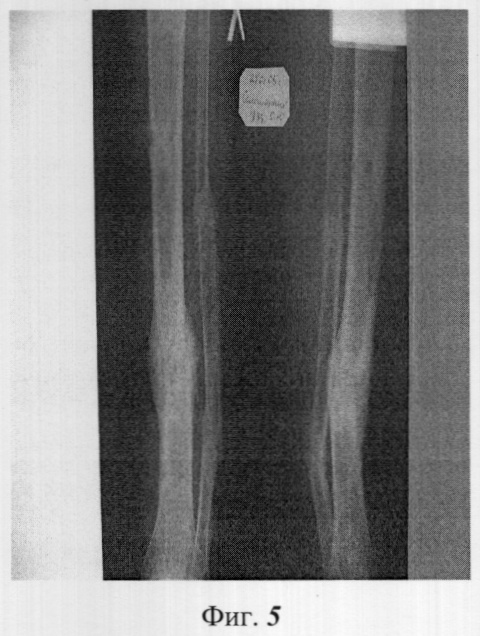

Фиг.5 – рентгенограмма конечности через год после операции.

В послеоперационном периоде больной активизирован, с 4-го дня полная нагрузка на конечность. Продолжительность лечения в стационаре – 10 дней. Через месяц проведена контрольная рентгенография (фиг.3) процесса сращения. Через 3,5 месяца аппарат демонтирован, трудоспособность восстановлена (фиг.4). Через год в зоне дефекта-псевдоартроза отмечалось сращение с перестройкой костной ткани и трансплантатов (фиг.5).